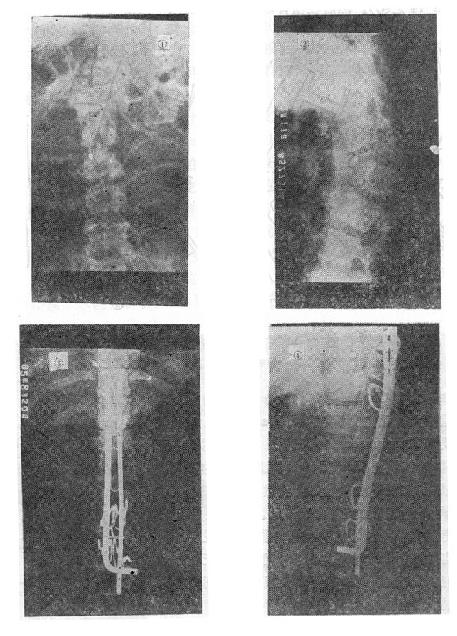

图73-12 垫枕背伸锻炼获良好结果 ①骨折初时;②背伸锻炼3个月后 (二)旋转型脊柱骨折的治疗 用Harrington棍法,不能矫正旋转,最好用Luque棍或Dick法进行矫正与固定。两根“L”型金属棍,放在棘突基底两侧,用每一个椎板下穿过的Luque钢丝固定到骨折部位上、下方各三个椎体椎板上,通过弯好弧度的Luque棍的杠杆作用和拧紧Luque钢丝所产生的矫正力,可以矫正旋畸形,并牢固固定骨折。如不合并神经系统症状,1周后即可下地活动。 (三)爆裂型骨折的治疗 如不合并严重的神经系统症状,损伤又在两周以内者,可以用双Harrington法,撑开矫正,或用Dick手术;可以获得满意的结果(图73-13)。复位后需融合相邻两个椎间隙,因为CT常显示在爆裂型骨折中,相邻的上、下两个椎间盘均有损伤,如不融合,日后取棍后会出现腰痛。使用本法时,如前纵韧带完整,则很容易恢复椎体前方的高度。但爆裂型骨折存在下述三种情况时,需行前路减压术:①合并神经系统症状较重者;②就诊较晚,已两周以上者(常常10天以上就复位比较困难);③脊柱CT扫描显示已有较大的骨折片突出椎管内,使髓腔管变窄超过30%以上者,预示后纵韧带已有明显损伤,使用后路手术方法已无法使骨折片复位。Kostuik复习了日本和多伦多治疗脊柱骨折的结果后证实,前路减压术能使膀胱、肛门及肢体功能得到更好的恢复。

图73-13 爆裂型骨折的治疗 ①术前,骨折脱位;②术后,侧位;③术后,正位 前路手术方法为病人取侧卧位,腰椎骨折由肾切口进入,胸腰段骨折则经切除第10肋之胸腹联合切口进入,结扎节段血管后,切开并向侧方推开椎前胸膜壁层,从腰椎侧方向椎体前方剥离骨膜,先掀起骨膜再进行骨折的处理,有助于防止血管损伤。然后切除骨折处的椎间盘,此时先找出椎间孔前缘,保护好神经和脊髓,再用咬骨钳咬除病椎骨质(保留作植骨用),靠后部分可用电钻磨(图73-14之①②)。对于旋入椎管腔内的骨片,可用刮匙将骨片旋转回原来的部位,减除脊髓的压迫(图73-14之③)。直至看到对侧硬脊膜,然后进行植骨。取一段腓骨嵌入植骨,在一助手将脊柱由后向前推顶的同时,将腓骨卡入,恢复椎体前缘高度(图73-14之④)。然后在植骨块的两侧再植入一些松质骨。